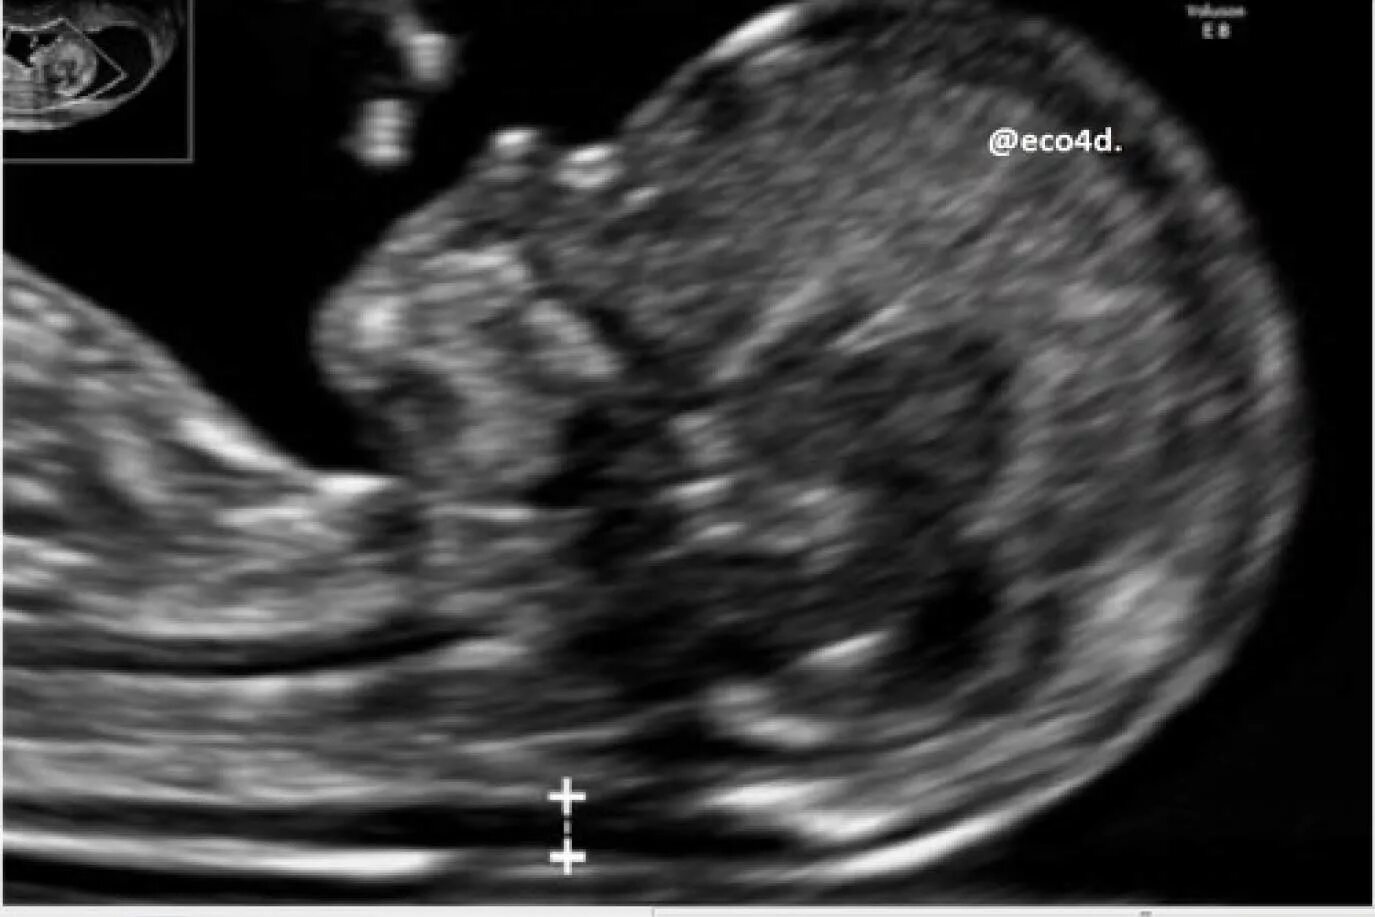

Воротниковое пространство 5